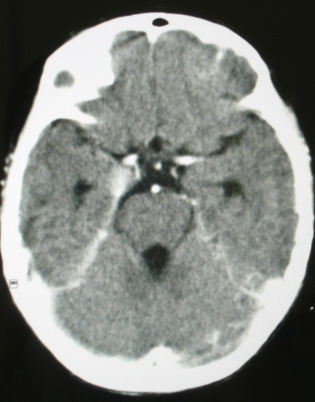

m/8y/,右侧眼睑下垂数日,发育良好,无外伤史,无头痛、恶心、呕吐,学习成绩良好。

ct意见:1、颅内血管畸形。2、右侧海绵窦血管瘤(颈内动脉海绵窦段动脉瘤)。3、脑萎缩。4、建议mr或dsa.

平扫片(骨窗未见异常)